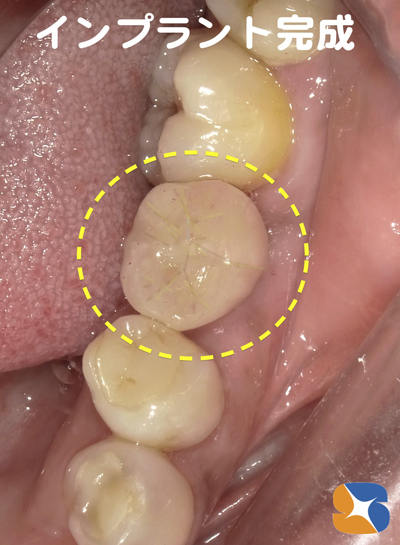

1ヶ月間、仮歯を入れて噛む練習をしてから、本番のセラミックの被せ物を装着しました。

まさか私がインプラントの歯で噛めるなんて!